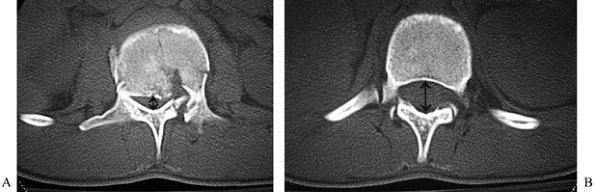

scan, by comparing the AP diameter of the normal spinal canal at an

fragment (26). The ratio of the injured to the intact diameters provides the percent compromise (Fig. 141.7).

The greatest compromise occurs at the level of the pedicles and upper

vertebral body. In type A and B burst fractures, the central portion of

the posterior cortex and body is driven back into the canal between the

two pedicles, which then prevent the fragment from reducing. Because of

the differing volumes of neural tissue in the canal at different

levels, compromise of greater than 50% may produce symptoms at the

thoracolumbar junction, whereas compromise of 85% or more may be well

tolerated at the lumbosacral junction (9). A CT scan will also demonstrate the presence and extent of posterior element disruptions (Fig. 141.8). Three-column injuries are

Figure 141.7. Canal dimension at injured level (A) is compared to adjacent normal level (B) to determine percent canal compromise.